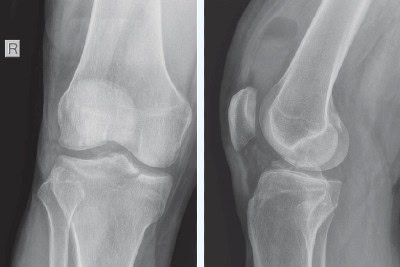

A 38-year-old otherwise healthy male presents to urgent care with acute right knee pain following a 6-foot fall from a ladder, landing directly on his right lower extremity 2 hours prior to arrival. He reports severe pain and the inability to bear weight since the injury. Physical examination reveals that he is afebrile with normal vital signs. Musculoskeletal exam is notable for moderate knee effusion with surrounding early ecchymosis, and medial joint line tenderness. There …